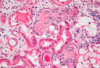

What do you see here?

Acute interstitial nephritis